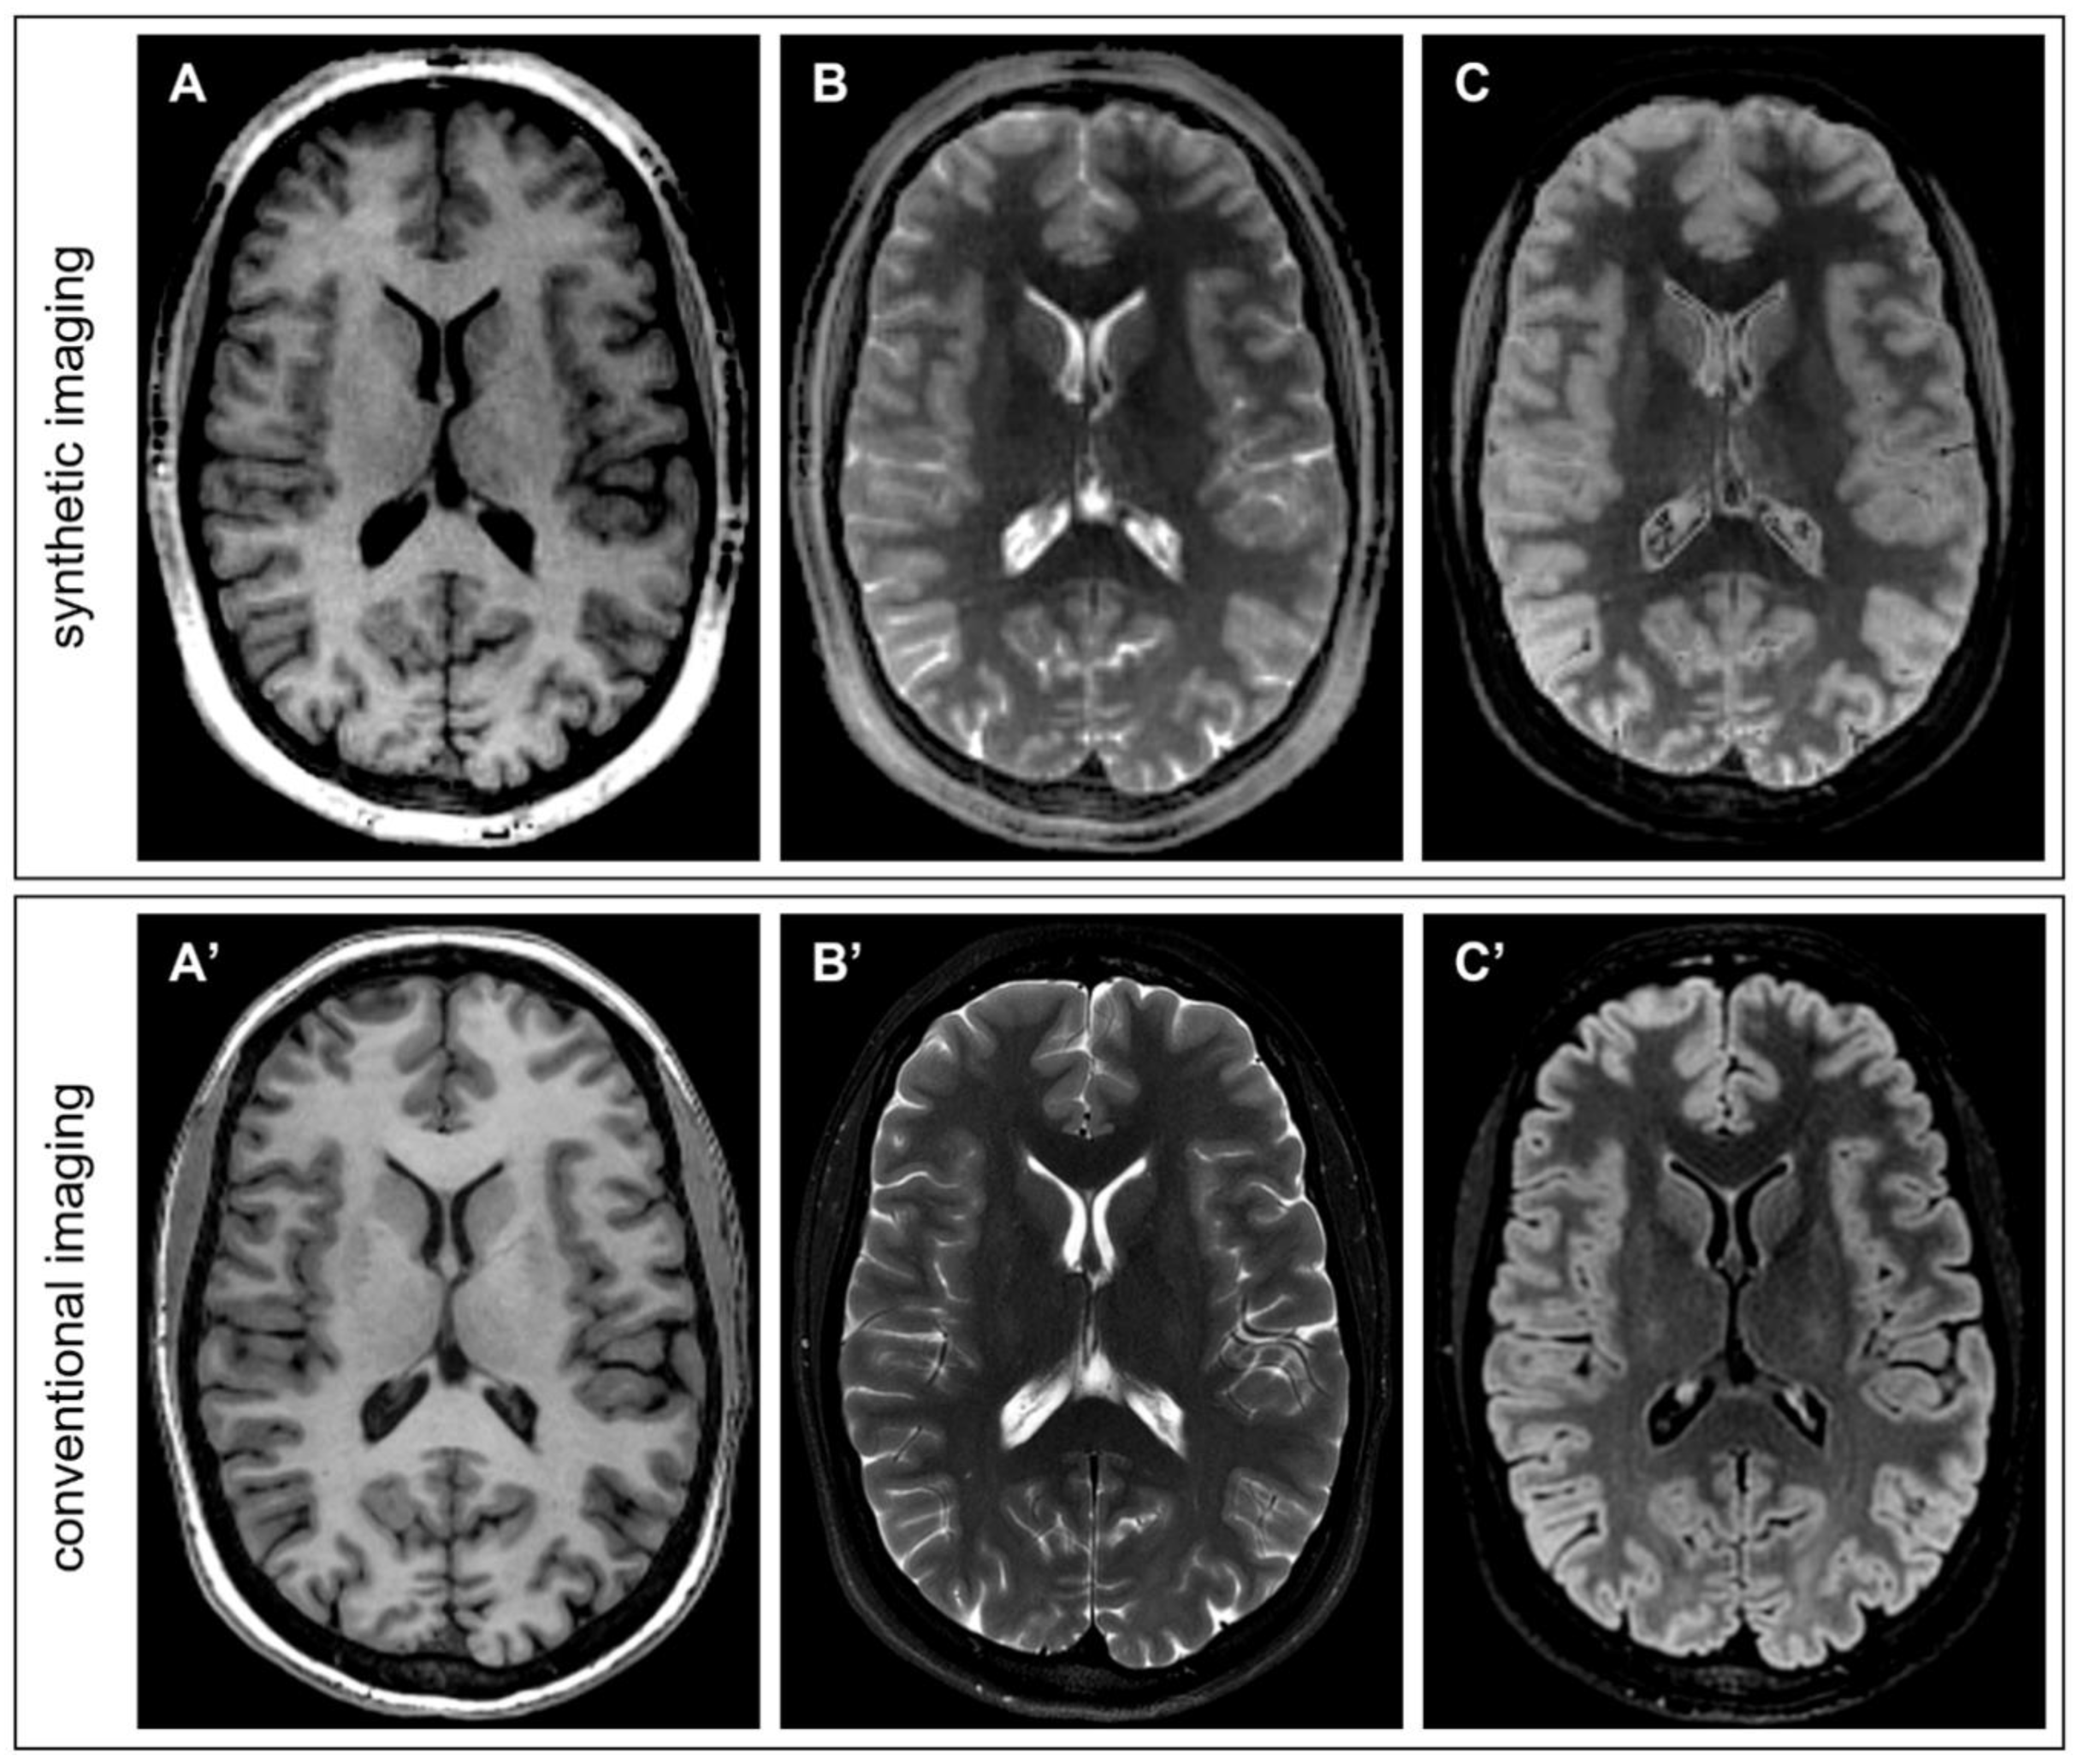

- Synthetic T1-weighted images simulating GRE (Gradient-recalled Echo) were synthesized with the following equation, incorporating the input maps of PD and T1 and setting the simulated acquisition parameter TR:

- Bias-free T1-weighted MPRAGE was synthesized by taking into consideration that B1 bias in QTI is incorporated in the PD map, which can be excluded from the formula, achieving a similar appearance to MP2RAGE uniform imaging [15]:

- Synthetic T2-weighted images simulating a SE (Spin Echo) acquisition were obtained as follows:

- Synthetic T2-FLAIR was obtained with a user-modified formula incorporating a coefficient TSAT, which enables the introduction of T1-weighting, which better mimics the one in conventional imaging: